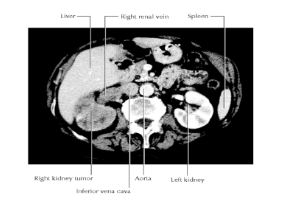

Describe Renal Cell Carcinoma:

Patient Presentation

Complication

Renal cell carcinomas:

Grow outward of the kidney into fat & fascia

Patient Presentation:

Most patients complain of blood in the urine (hematuria), pain in the infrascapular region (loin), and a mass.

Complication:

invade the renal vein Spread to the inferior vena cava, right atrium, and across the tricuspid valve into the pulmonary artery.